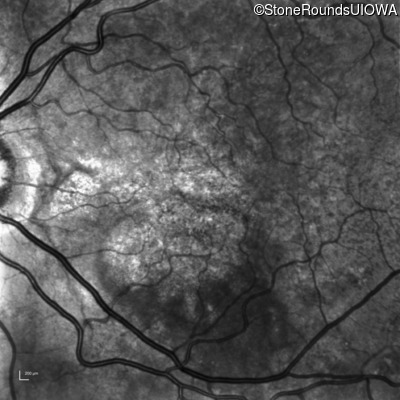

Age at visit: 58 years